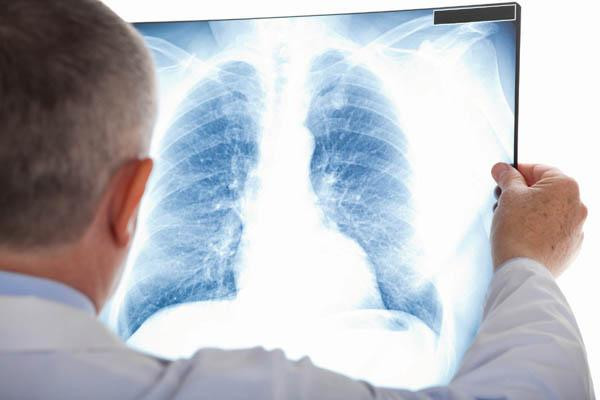

Chuyên gia dịch tễ cho hay, chỉ trong 10 ngày đầu năm 2020, Viện đã tiếp nhận 13 mẫu bệnh phẩm viêm phổi nặng do vi rút và làm các xét nghiệm cần thiết, xác định ngay các ca viêm phổi nặng do cúm chứ không phải do nguyên nhân nào khác. Các BV, cơ sở y tế ngay ở tuyến dưới cũng vẫn đang tiếp tục sàng lọc phát hiện sớm các ca bệnh nặng để chủ động ứng phó, gửi mẫu bệnh phẩm đến các Viện Vệ sinh dịch tễ Trung ương.

"Xét nghiệm là công cụ cực kỳ quan trọng, chúng ta cũng đã có kinh nghiệm xử lý các vụ dịch, đặc biệt là dịch SARS. Năng lực xét nghiệm, chẩn đoán tin cậy, hiện nay, phòng an toàn sinh học cấp 3 có đủ khả năng đối phó với bệnh mới, bệnh lạ chưa rõ nguyên nhân. Các chuyên gia đầu ngành về vi rút học vẫn đang túc trực sẵn sàng..."- PGS. Dương cho biết thêm.

Tuy nhiên, ông Dương cũng nêu khó khăn chung của việc xét nghiệm, chẩn đoán hiện nay là thiếu mồi đặc hiệu, trình tự gen, trứng dương để có thể chỉ đích danh loại vi rút này.